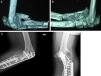

Caso 1Paciente de sexo femenino, de 30 años, diestra, con antecedente de tumor de células gigantes en húmero distal derecho. Inicialmente se realizó resección local del tumor y reconstrucción del codo con aloprótesis, que presentó infección temprana y requirió retirada de la prótesis y colocación de espaciador de cemento. Al cabo de 1 año se realizó nuevo intento de reconstrucción con endoprótesis en codo derecho, pero presentó recaída infecciosa temprana. Se retiró la endoprótesis y se aplicó espaciador de cemento, el cual tuvo que ser retirado por infección supurativa no controlada. Durante 7 años presentó recaídas infecciosas tratadas con antibióticos locales sin información sobre aislamientos. A los 9 años del procedimiento inicial se realiza curetaje óseo y toma de muestras para cultivos, de los cuales se obtiene aislamiento de Staphylococcus aureus sensible a oxacilina en húmero y cúbito. En la radiografía se identifica hueso escleroso con imágenes de secuestros y se define en conjunto con Infectología que no hay opción de tratamiento antibiótico si no se logra una erradicación de la infección (fig. 1).